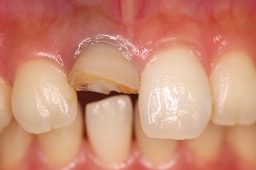

症例写真 セラミック治療前後

・ 白い歯を保ちたい!

・ 治療後の歯を目立たなくしたい!